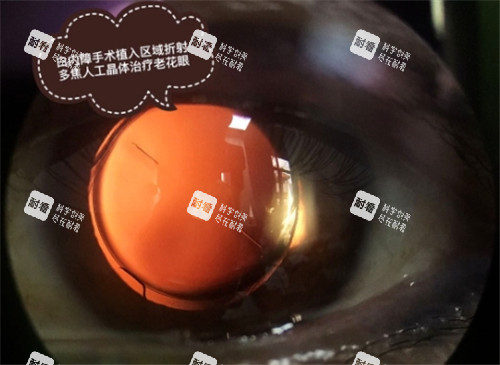

医院投入5000多万元引进30余台(件)10万元以上的科技设备,其中包括鲁西-南仅有一台海内外可靠的飞秒激光白内障治疗仪,始创了白内障手术的无刀时代。

常规开展超声乳化联合人工晶体植入术,这是目前白内障诊疗领域的主流技术,具有创伤小、改善比较快等优势,年手术量突破2000例。

免费手术的核心是“手术费全免”,仅有的自费项目是人工晶体的选择,患者可根据自身需求和经济情况挑选不同类型的晶体。